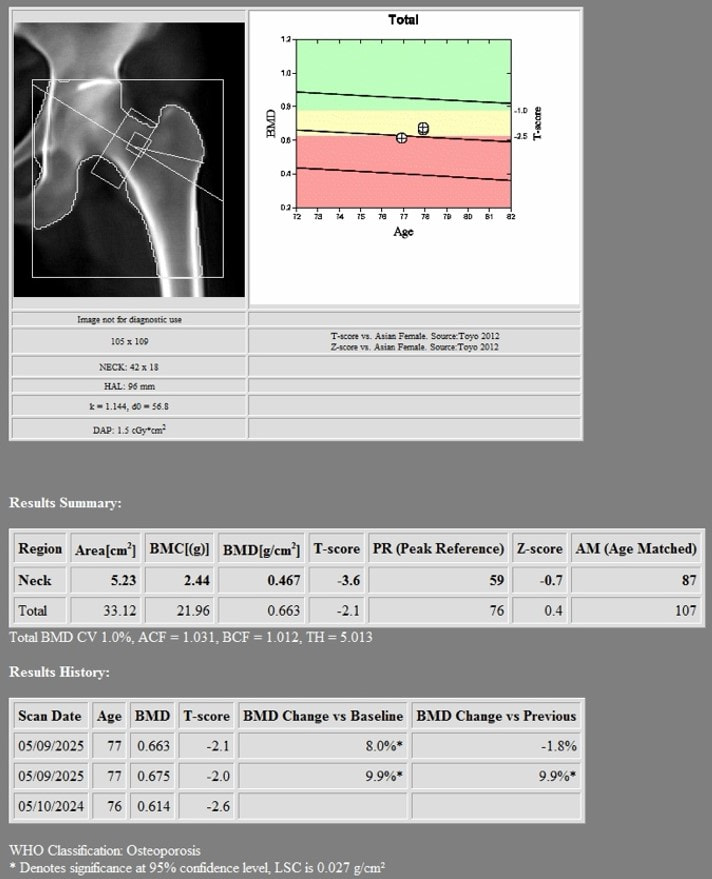

1st DXA Scan (Before Romosozumab treatment)

2nd DXA Scan (1 year after romosozumab treatment)

Hologic Horizon W

- LSC AP Spine 0.022 g/cm2

- LSC Neck of Femur 0.028 g/cm2

- LSC Total Hip 0.027 g/cm2

Changes in BMD after completing 1 year of Romosozumab

- Lumbar Spine = +0.121 g/cm2 (22.04%)

- Neck of Femur = +0.03 g/cm2 (6.86%)

- Total Hip = +0.049 g/cm2 (7.98%)

There was an increase in the BMD after she underwent 1 year of treatment with Romosozumab:

- Lumbar Spine: +0.121 g/cm2 (22.04%, LSC 0.022)

- Neck of Femur: +0.03 g/cm2 (6.86%, LSC 0.028)

- Total Hip: +0.049 g/cm2 (7.98%, LSC 0.027)

All the increases in these three parameters were higher than the respective LSC.

- DXA scan showed that the changes in BMD after completing 1 year of romosuzumab was: